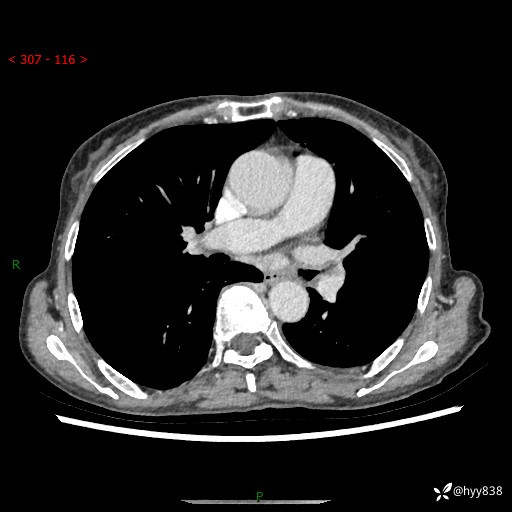

胸部CT平扫+增强